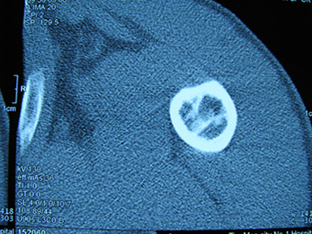

标题: X6404B:肱骨骨质破坏(CT片) [打印本页]

标题: X6404B:肱骨骨质破坏(CT片)

男,50岁,左肩部轻微疼痛,活动不便5个月就诊,近十天加重,无红肿热,间断理疗治疗无好转,既往5个月前左肩轻微拉伤史

骨巨?动脉瘤样骨囊肿?

内生软骨瘤。

内生软骨瘤。

内生软骨瘤?-----------

年纪大了,先要排除转移瘤。

髓腔内软组织肿块并斑片状钙化,考虑高分化软骨肉瘤可能性大。

考虑骨巨或动脉瘤样骨囊肿。

内生软骨瘤可能性大,期待结果。

孤立性骨囊肿。

内生软骨瘤可能性大

其内可见钙化,考虑软骨源性肿瘤,内生软骨瘤可能

但由于年龄较大,恶性软骨肉瘤待排

肱骨头内巨大软组织肿块并斑片状钙化,内生软骨瘤?骨巨细胞瘤?软骨粘液样纤维瘤?期待结果!

髓腔内软组织肿块并斑片状钙化,考虑高分化软骨肉瘤可能性大。

内生软骨瘤可能性大

肱骨头内巨大软组织肿块并斑片状钙化,内生软骨瘤?骨巨细胞瘤?软骨粘液样纤维瘤?期待结果

考虑内生软骨瘤?骨巨细胞瘤?

内生软骨瘤?骨巨细胞瘤?

先要排除转移瘤。